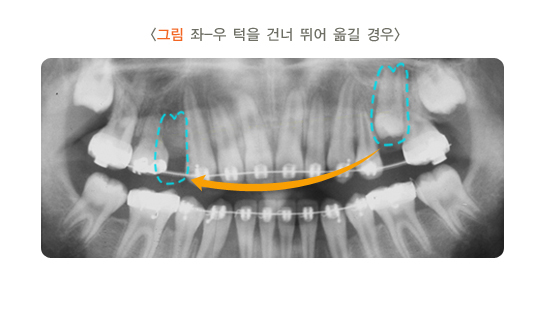

또한 나오고 있는 치아에 홈메우기를 적용하게 될 경우 도포가 불완전하게 시행될 수 있습니다. 완전히 맹출되지 않은 부위의 하방에 재료가 넘치게 되면 음식물이 끼거나 치태가 생겨 우식이 더 쉽게 발생할 수 있습니다. 따라서 치아가 충분히 나온 다음 도포해 주는 것이 바람직합니다.